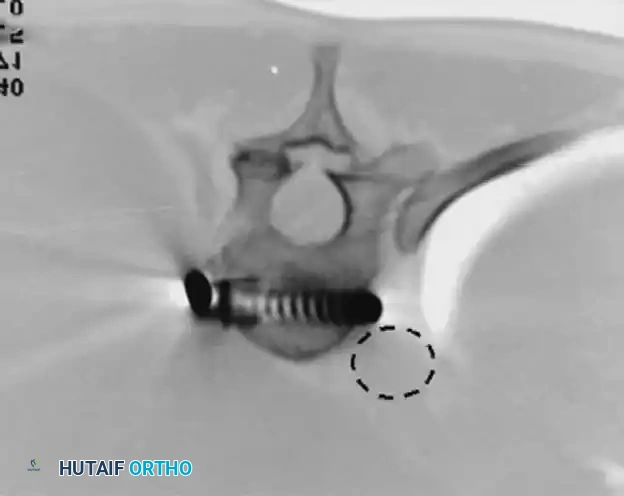

* Biomechanical Failures: Without meticulous attention to rod contouring and structural grafting, a kyphosing effect can occur, obliterating normal lumbar lordosis. Furthermore, because anterior screws rely on relatively cancellous vertebral body bone, proximal screw pullout or dislodgment is a known risk.

* Late Complications: Retroperitoneal fibrosis and vascular impingement from prominent instrumentation.

(CT imaging demonstrating the critical proximity of anterior thoracic screws to the descending aorta. Bicortical purchase must be executed with extreme caution.)